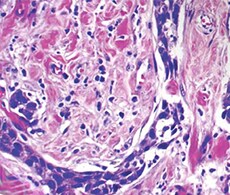

The heterogeneous nature of tumor biopsies can make it difficult to generate useful genomic data from whole tissue samples. Laser capture microdissection (LCM) is a powerful technique that has become instrumental to researchers interested in comparing the molecular profiles of tumor tissue to surrounding non-tumor cells, thereby unlocking hidden molecular signatures in individual patient tumor samples and leading the way for tailored treatment and personalized medicine. The gentle IR laser of the Arcturus LCM systems preserves tissue morphology and genetic content of captured and neighboring cells, providing researchers with an effective tool to easily verify captured material while simultaneously preserving biomolecule integrity.